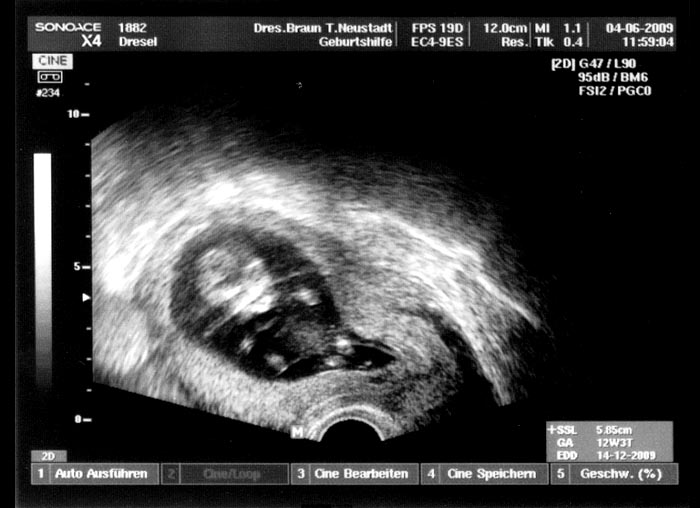

6. Ultraschallaufnahme